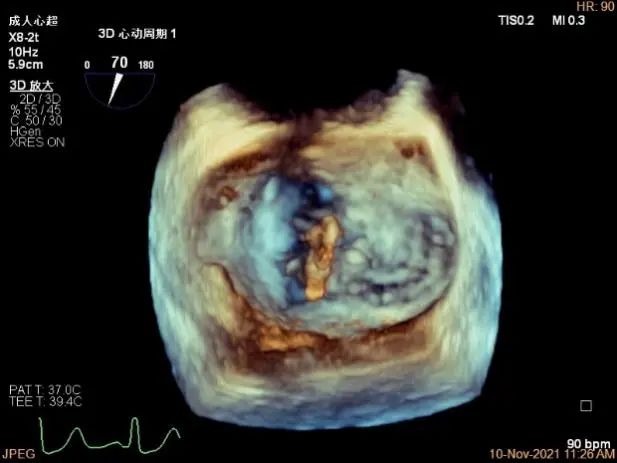

3D MV View:P1区瓣体瘤形成并中央型破裂孔,脱垂从P1到P2区,脱垂宽度13.1mm,破裂孔大小4.1×5.6mm